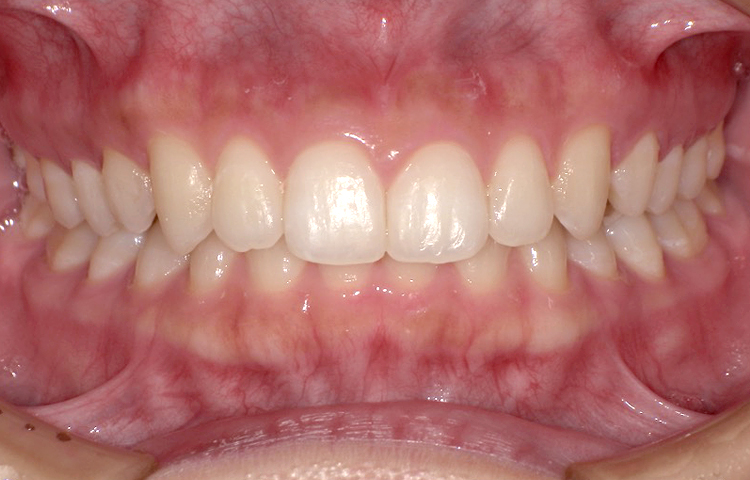

治療前

治療後

| 主訴 | 上の前歯のガタつきが気になるので前歯だけ綺麗にして欲しい |

|---|---|

| 治療 期間 |

約6ヶ月 |

| 治療費 | 165,000円(税込)/調整費用別途 |

| 治療 内容 |

上の前歯部にワイヤーを着けて進めていく、プチ矯正で施術。 |

| 治療の リスク |

見た目を綺麗にする目的で短期間で仕上げる為噛み合わせは矯正しない。 |